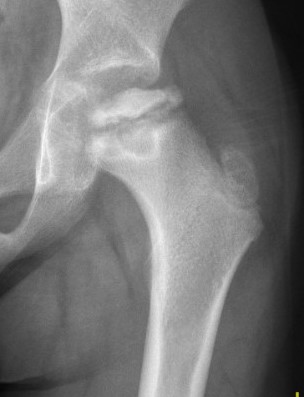

Femoral Varus Osteotomy (FVO)

Indications

Herring grade B or B/C

> 8 years at age on onset

Full containment of cartilaginous head

No hinge abduction

Persisting cova vara

Leg length discrepancy

Over-riding greater trochanter